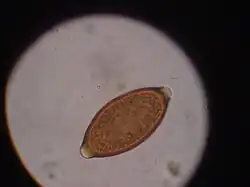

Trichuris vulpis is a whipworm that lives in the large intestine of canines in its adult stages. Out of different types of worms, Trichuris vulpis is one of the smaller worms with a size ranging from 30–50 mm in length. As the name suggests, the worm has a whip-like shape with distinct features including a small, narrow anterior head, which is the digestive part of the worm, and a larger posterior tail, which is the reproductive part of the worm. Eggs from T. vulpis are oval shaped with bipolar plugs and contain a thick outer shell. Their sizes range from 72–90 μm in length and 32–40 μm in width.[1] Because of their thick outer shell, T. vulpis eggs are very resistant to environmental extremes such as freezing or hot temperatures, thus allowing for their long viability in the outside world.[2]

Infection of this parasite can be confirmed with detection of eggs in the canine's feces. Adult T. vulpis females can produce more than 2,000 eggs per day. These eggs can be detected in the canine's feces by the fecal flotation method.[14] This method utilizes the differences of specific gravity of eggs, fecal debris, and the flotation solution.[15] Although these eggs are dense, the use of proper fecal flotation technique using a sugar solution and centrifugation can increase the chances of identifying these eggs in a fecal sample.[16] Multiple fecal samples may need to be tested as the eggs may be shed periodically.[17]